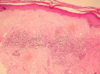

What is this an image of?

Normal breast: Ducts lined by double layer of epithelial cells and surrounded by layer of myoepithelial cells

What is this an image of?

Normal breast